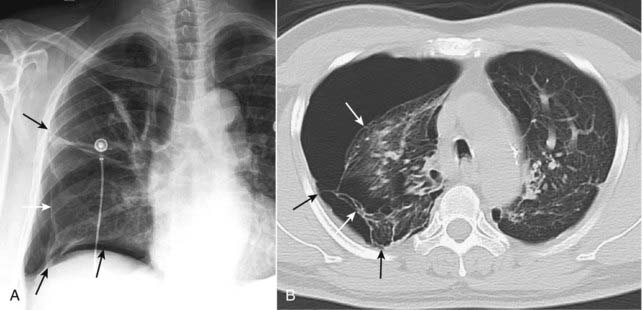

Figure 8-3 Pneumothorax with pleural adhesions.

Lung markings may be visible on a conventional radiograph of the chest, distal to the visceral pleural line if pleural adhesions are present. In (A), a pneumothorax (solid white arrows) is prevented from collapsing the lung by pleural adhesions (solid black arrows). On a CT scan (B), the pleural adhesions (solid black arrows) are seen tethering the lung (solid white arrows) to the parietal pleura. Adhesions most frequently result from prior infection or blood in the pleural space.

On conventional radiographs, it may be possible to visualize lung markings in front or in back of the pneumothorax and to overlook the presence of a pneumothorax because lung markings appear to extend to the chest wall.

Absence of lung markings alone is not sufficient for the diagnosis of pneumothorax nor is the presence of lung markings distal to the visceral pleural line sufficient to eliminate the possibility of a pneumothorax.